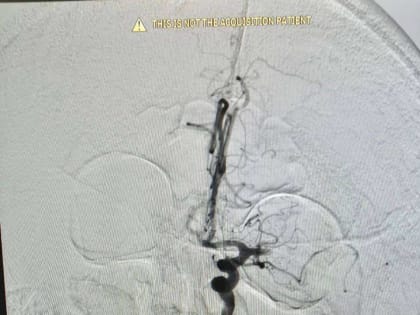

В Орске врачи спасли 74-летнего мужчину от ишемического инсульта

При помощи современных технологий ему удалили тромб в внутримозговой артерии.